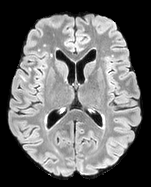

The detection of new multiple sclerosis (MS) lesions is an important marker of the evolution of the disease. The applicability of learning-based methods could automate this task efficiently. However, the lack of annotated longitudinal data with new-appearing lesions is a limiting factor for the training of robust and generalizing models. In this work, we describe a deep-learning-based pipeline addressing the challenging task of detecting and segmenting new MS lesions. First, we propose to use transfer-learning from a model trained on a segmentation task using single time-points. Therefore, we exploit knowledge from an easier task and for which more annotated datasets are available. Second, we propose a data synthesis strategy to generate realistic longitudinal time-points with new lesions using single time-point scans. In this way, we pretrain our detection model on large synthetic annotated datasets. Finally, we use a data-augmentation technique designed to simulate data diversity in MRI. By doing that, we increase the size of the available small annotated longitudinal datasets. Our ablation study showed that each contribution lead to an enhancement of the segmentation accuracy. Using the proposed pipeline, we obtained the best score for the segmentation and the detection of new MS lesions in the MSSEG2 MICCAI challenge.